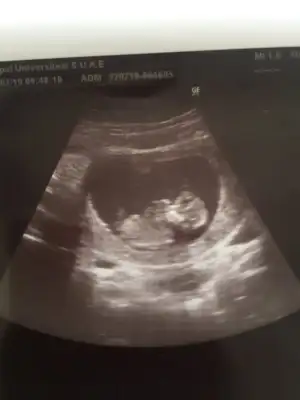

Kızlar benim ultrasonumu yanıtlamıştınız bi arkadaşımın ultrasonunu yükleyeceğim onuda yorumlar mısınız? Şimdiden çok teşekkürler🤗

merhaba 12+0 acaba yorumlayabilir misiniz ben cıkintı gormedim